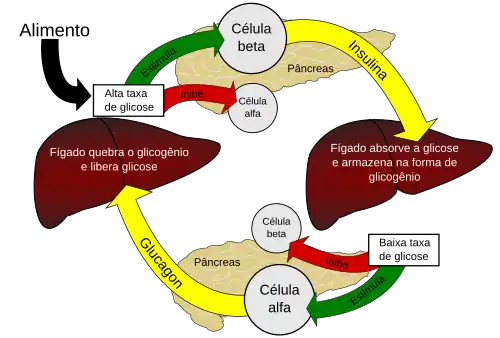

O pâncreas é o órgão responsável pela produção do hormônio denominado insulina. Este hormônio é responsável pela regulação da glicemia (glicemia: nível de glicose no sangue). Para que as células das diversas partes do corpo humano possam realizar o processo de respiração aeróbica (utilizar glicose como fonte de energia), é necessário que a glicose esteja presente na célula. Portanto, as células possuem receptores de insulina (tirosina quínase) que, quando acionados "abrem" a membrana celular para a entrada da glicose presente na circulação sanguínea. Uma falha na produção de insulina resulta em altos níveis de glicose no sangue, já que esta última não é devidamente dirigida ao interior das células.

Visando manter a glicemia constante, o pâncreas também produz outro hormônio antagônico à insulina, denominado glucagon. Ou seja, quando a glicemia cai, mais glucagon é secretado visando restabelecer o nível de glicose na circulação. O glucagon é o hormônio predominante em situações de jejum ou de estresse, enquanto a insulina tem seus níveis aumentados em situações de alimentação recente.

Como a insulina é o principal hormônio que regula a quantidade de glicose absorvida pela maioria das células a partir do sangue (principalmente células musculares e de gordura, mas não células do sistema nervoso central), a sua deficiência ou a insensibilidade de seus receptores desempenham um papel importante em todas as formas da diabetes mellitus.

A insulina é liberada no sangue pelas células beta (células β) do pâncreas em resposta aos níveis crescentes de glicose no sangue (por exemplo, após uma refeição). A insulina habilita a maioria das células do corpo a absorverem a glicose do sangue e a utilizarem como combustível, para a conversão em outras moléculas necessárias, ou para armazenamento. A insulina é também o sinal de controle principal para a conversão da glicose (o açúcar básico usado como combustível) em glicogênio para armazenamento interno nas células do fígado e musculares. Níveis reduzidos de glicose resultam em níveis reduzidos de secreção de insulina a partir das células beta e na conversão reversa de glicogênio a glicose quando os níveis de glicose caem.